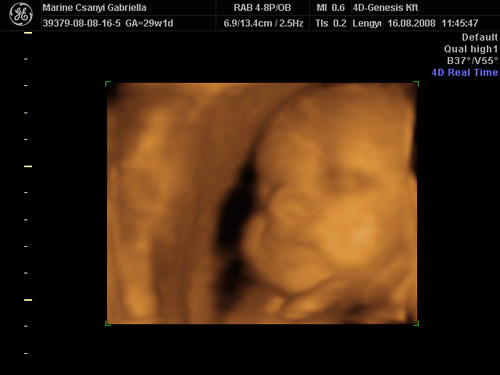

Voltam megint 4D-n. Állítólag 1400g és a mérete 29-30 hetesnek felel meg. Rakok fel képeket.

Kép Kép

A2. képen éppen mosolyog. Olyan jó volt így látni. Lemérték a talpát. Már 5cm. :D